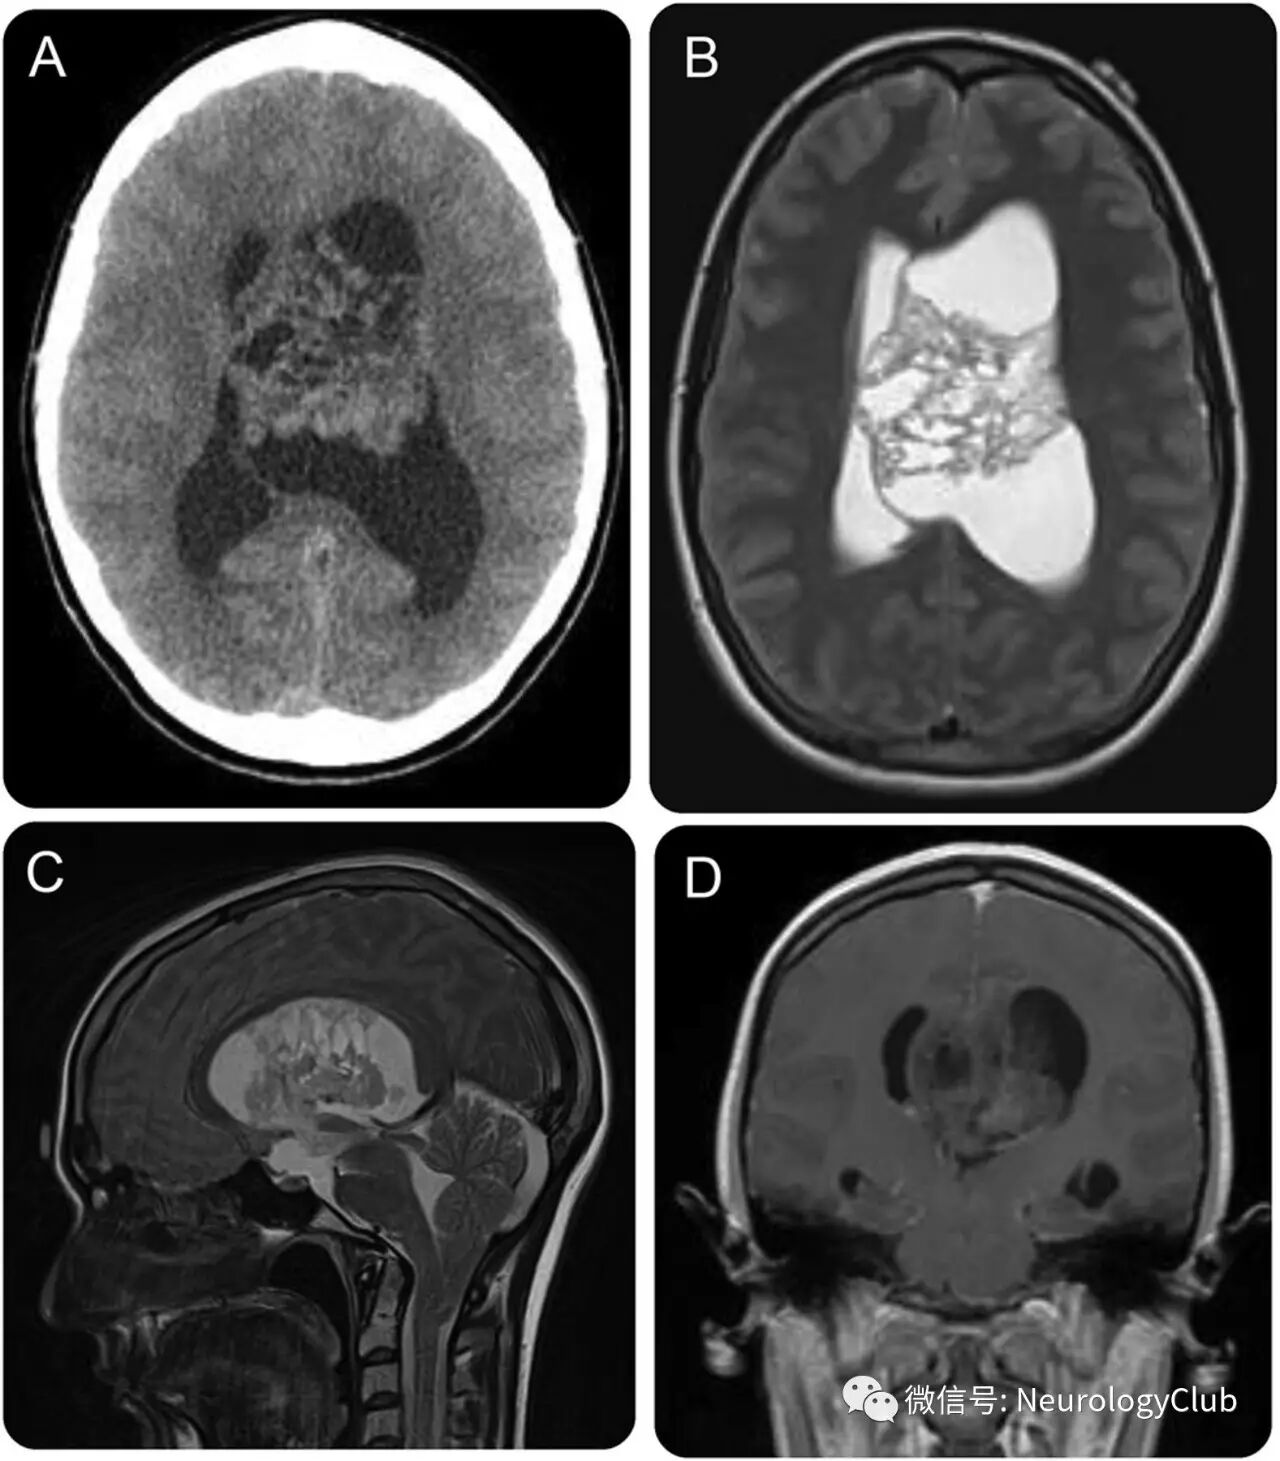

20余岁女性,表现为进行性加重的头痛,闭经和恶心6月。神经系统查体可见找词困难,右侧肢体轻度无力以及右侧轻度忽视。影像学提示左侧脑室内复杂的囊性不均匀强化的肿块,延伸累及Monro孔(图)。

(图:A:CT;B-C:T2WI;D:增强T1;可见5×5×4cm囊性肿块,导致脑积水;偶见存在大约2cm的小脑扁桃体下移[C],符合Chiari I畸形;临床表现的闭经可能因颅内压升高,鞍上池扩大间接压迫以及肿瘤直接作用于下丘脑所致)

MRI可以更好地显示中枢神经细胞瘤的范围,特别在矢状位和冠状位扫描对判断肿瘤范围和起源部位有很大价值。实性部分T1WI呈不均匀等低信号,T2WI 呈不均匀高信号;坏死、囊变部分呈更长T1、长T2信号;出血、钙化或肿瘤血管等有其相对特征性的信号表现;肿瘤形态不规则,增强扫描多呈较明显强化,其中可见迂曲粗大的血管影明显强化。周围水肿罕见,双侧或同侧脑室扩大。